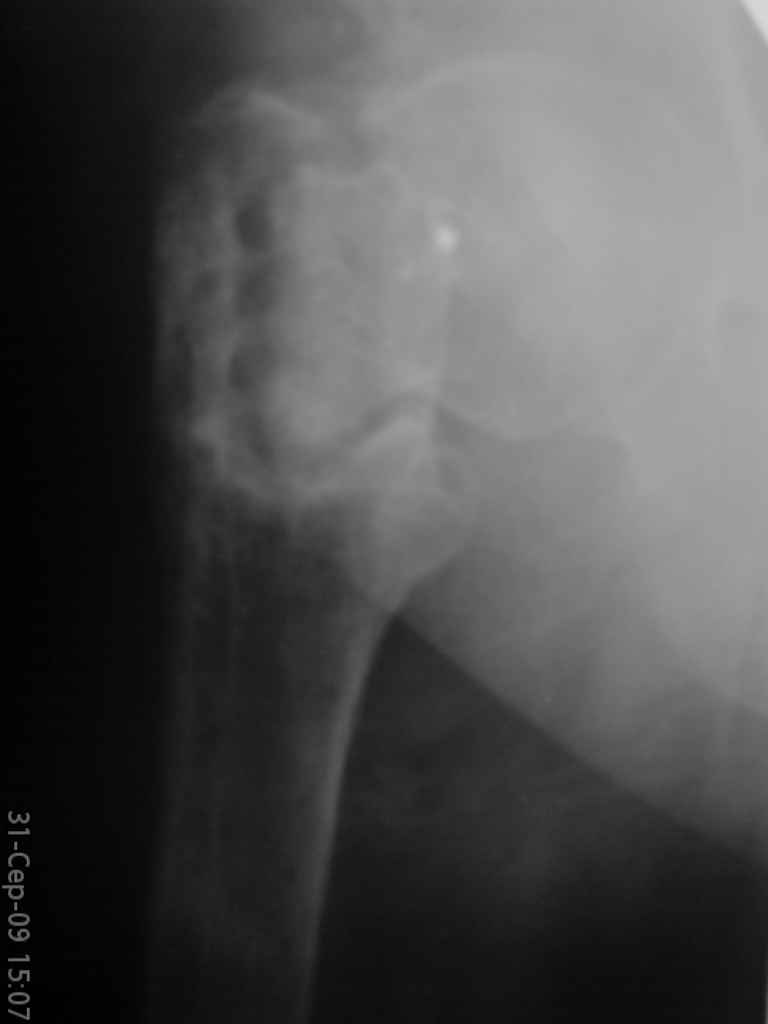

Уважаемые коллеги, помогите определиться с тактикой лечения. Больная, 62 года,жалуется на боли,неопорность левой ноги. Ходит с помощью костылей, укорочение ноги 3 см. Два года назад была оперирована кокой-то накостной пластиной, пластину удалили 4 мес назад. Вопрос такой: предлагать эндопротезирование или делать МОС (что-то по типу стержня Gamma)?За качество снимков извините, по данным МРТ - головка живая

На прошлой неделе оперировали похожего пациента. 2 года после неудачного остеосинтеза PFN в другом регионе. После удаления остатков железа выявилось несращение вертельной области.

>по данным МРТ - головка живая

Исследования показывают, что даже при частичном остеонекрозе головки бедра вальгусная остеотомия положительно влияет на восстановление кровообращения.

Секрет успеха в более благоприятной механике, за счет установки линии перелома в более горизонтальное положение. Вальгусная остеотомия создает необходимые механические условия для сращения ложного сустава в шейке и в вертельной области, а также восстанавливает длину конечности. Но любая вальгизирующая операция приведет к неизбежному вальгусу конечности.